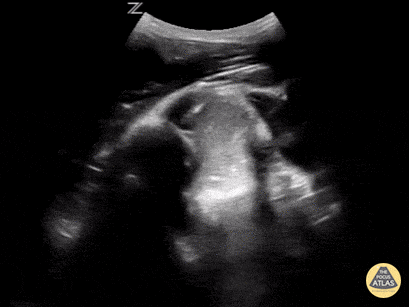

One Minute Image Review

One-Minute Image Review: High yield bite sized learning! Voice annotation of both normal and abnormal point of care ultrasound clips!